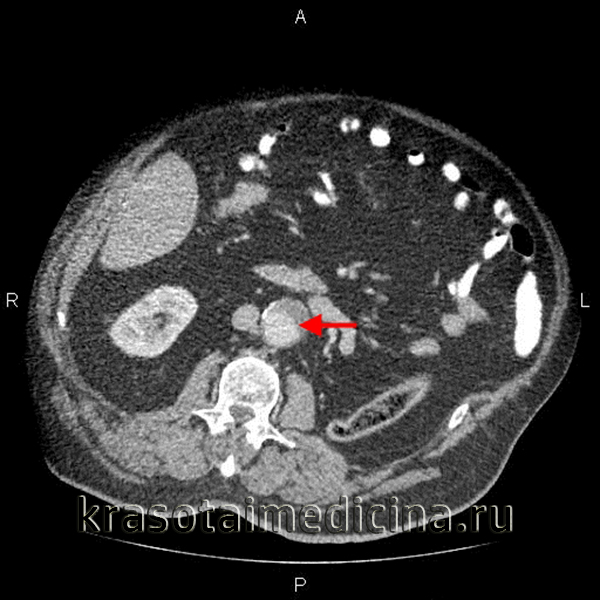

КТ-ангиография аорты. Аневризма брюшной аорты над бифуркацией. Просвет аневризмы (красная стрелка), пристеночный тромб (зеленая стрелка).

- Компьютерная томография. КТ (МСКТ) грудной/брюшной аорты позволяет точно и наглядно представить аневризматическое расширение, выявить наличие расслоения и тромботических масс, парааортальной гематомы, очагов кальциноза.